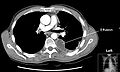

A pleural effusion appears as an area of whiteness on a standard posteroanterior chest X-ray.[7] Normally, the space between the visceral pleura and the parietal pleura cannot be seen. A pleural effusion infiltrates the space between these layers. Because the pleural effusion has a density similar to water, it can be seen on radiographs. Since the effusion has greater density than the rest of the lung, it gravitates towards the lower portions of the pleural cavity. The pleural effusion behaves according to basic fluid dynamics, conforming to the shape of pleural space, which is determined by the lung and chest wall. If the pleural space contains both air and fluid, then an air-fluid level that is horizontal will be present, instead of conforming to the lung space.[8] Chest radiographs in the lateral decubitus position (with the patient lying on the side of the pleural effusion) are more sensitive and can detect as little as 50 mL of fluid. At least 300 mL of fluid must be present before upright chest X-rays can detect a pleural effusion (e.g., blunted costophrenic angles).

Chest computed tomography is more accurate for diagnosis and may be obtained to better characterize the presence, size, and characteristics of a pleural effusion. Lung ultrasound, nearly as accurate as CT and more accurate than chest X-ray, is increasingly being used at the point of care to diagnose pleural effusions, with the advantage that it is a safe, dynamic, and repeatable imaging modality.[9] To increase diagnostic accuracy of detection of pleural effusion sonographically, markers such as boomerang and VIP signs can be utilized.[10]